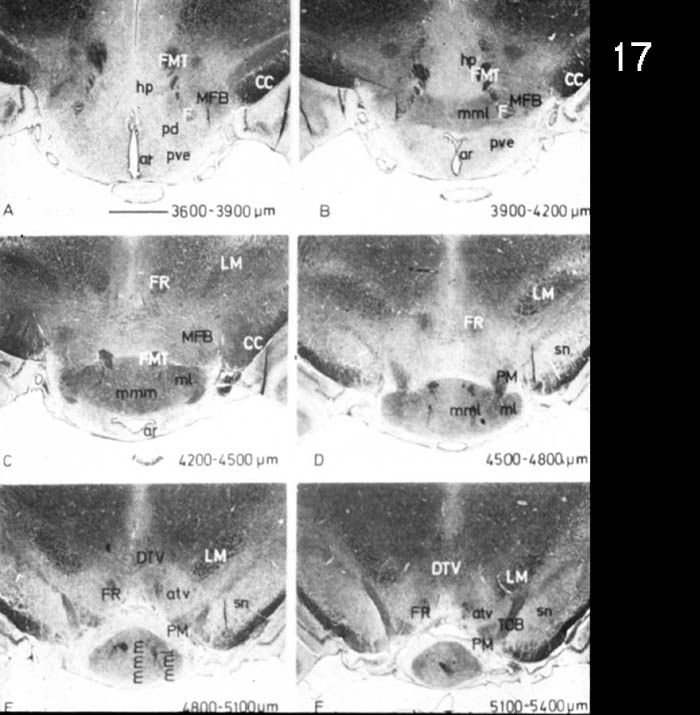

Figure 4 Figure 5 Figure 6 Figure 7 Figure 8 Figure 9 Figure 10 Figure 11

Figure 12 Figure 13 Figure 14 Figure 15 Figure 16 Figure 17